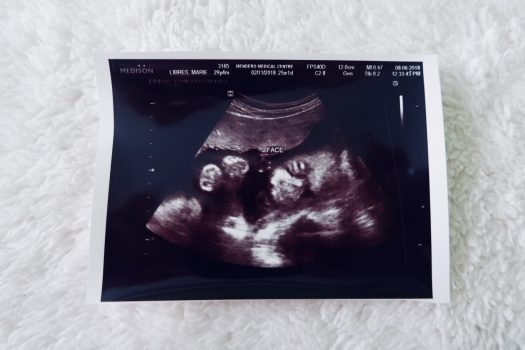

I had my Congenital Anomaly Scan (CAS) last 06th August 2018 at 24th weeks. [Congenital Anomaly Scan is different from the normal pregnancy ultrasound, the main purpose of the CAS is to check that your baby is developing normally. It takes a close look at your baby, your womb (uterus) and where the placenta is lying]. In my case, I personally asked my OB during my first prenatal check-up for this kind of test to check my baby for any possible condition problem. My OB informed me that I needed to wait ‘till the 20th weeks to undergo this test when the fetus has already developed organs and other body parts.

At 24th weeks, I was scheduled to have the CAS. I was so confident and so calm while waiting inside the Ultrasound Room and was so excited to see my baby on the monitor and to find out my baby’s gender. The OB-Gyne performing the scan checked everything from the measurement to every important fetal detail while dictating to her assistant all the information/result using terms I know nothing about. I was just listening without a clue if it’s something good or something bad. When the OB shifted the monitor in front of me to let me see all important parts of my baby’s body (spinal cord, internal organs, and physical features) the entire time my heart was jumping out of joy. She showed each part and would tell that its size and position are okay and normal, she showed me one by one and naming the facial features, she counted the fingers and toes for me, and lastly showed and revealed to me the gender. On that day, God answered two of my constant prayers, to bless me a healthy baby boy and to give me a very good result about my baby’s growth and development. Indeed, God does wonders and miracles. I feel His presence with me inside the room on that day.

That day, 06th August 2018, was the day God performed His miracle to my life by keeping my baby safe and sound inside my womb and not letting the medicine affect my growing baby. I was the happiest person on that day. All glory to God.